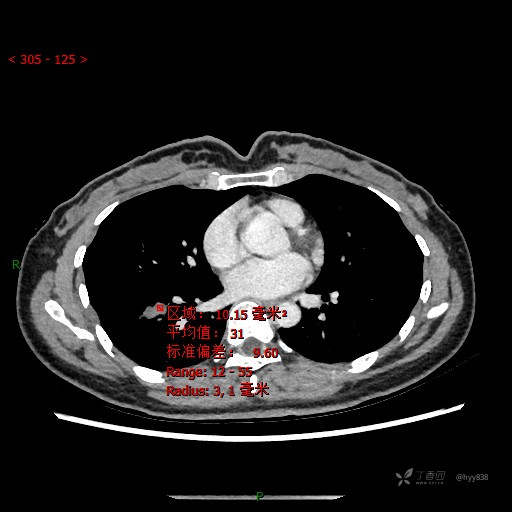

增强动脉期

CT值